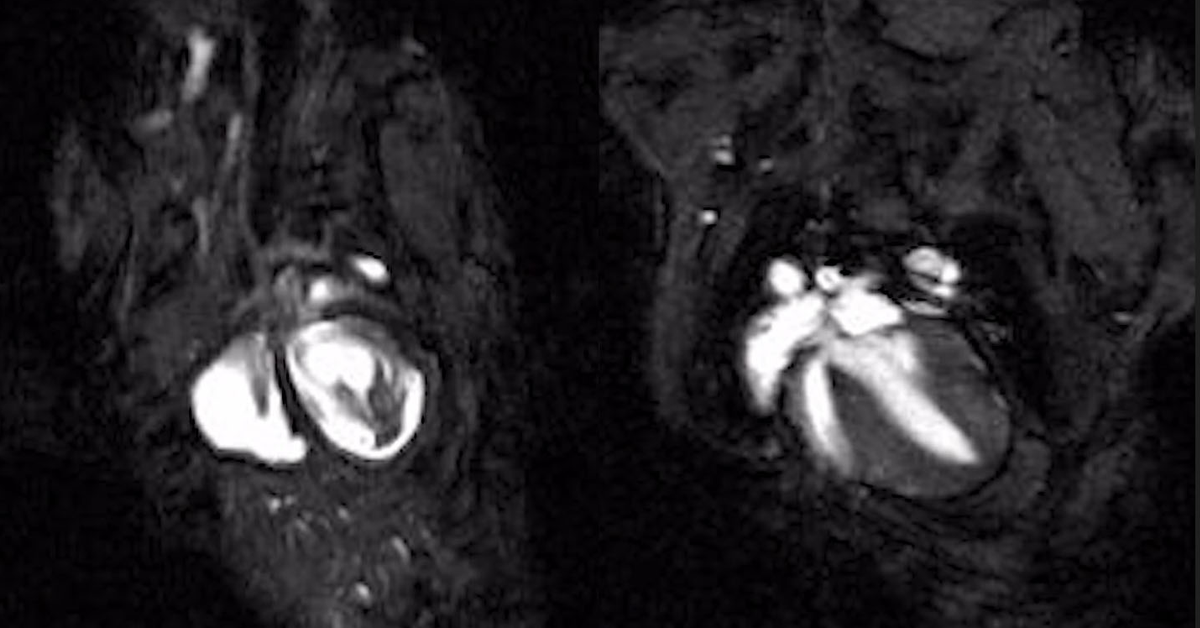

MRI photo of mouse's beating heart

Cardiac magnetic resonance imaging (MRI) videos of beating hearts in an inherited arrhythmogenic cardiomyopathy mouse model, shown untreated (Left) and after connexin-43 gene therapy treatment (Right), illustrating repair of impaired heart function. Image: UC San Diego Health Sciences